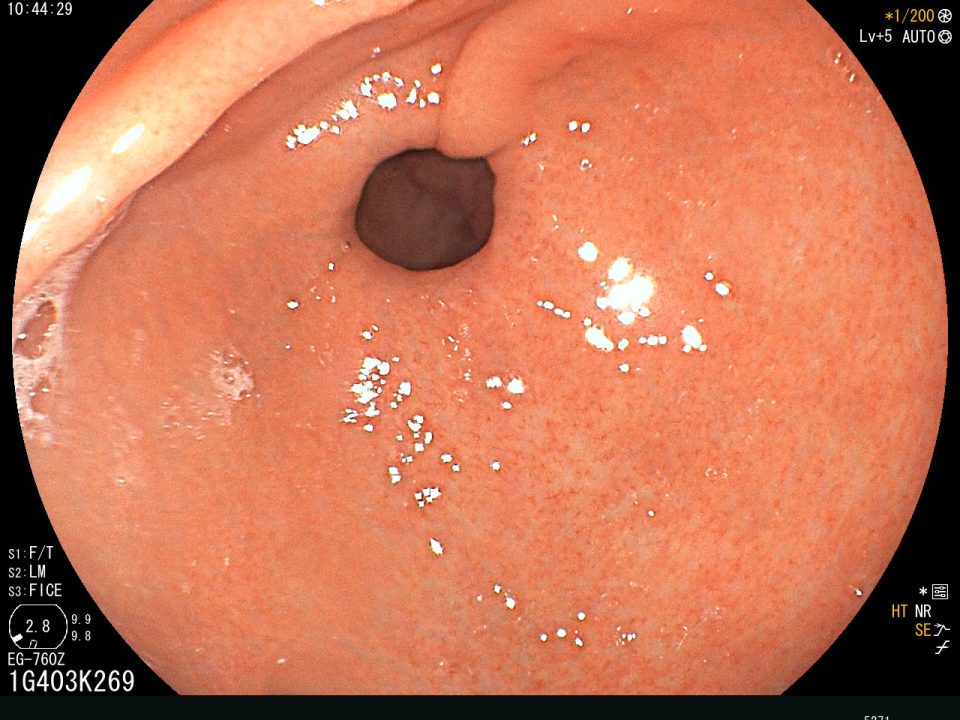

Como la metaplasia intestinal es considerada un estadio de la secuencia temporal de lesiones histológicas gradualmente inducidas por H. pylori, su regresión después de la erradicación es controversial. Algunos estudios sugieren que la erradicación de H. pylori puede mejorar la infiltración de neutrófilos y la metaplasia intestinal en la mucosa gástrica e inhibir el desarrollo de nuevos carcinomas. Pero, parecería que solamente la erradicación de H. pylori no es la respuesta y que otras intervenciones pueden ser necesarias para revertir esta condición. Estudios epidemiológicos indican que una ingesta de frutas cítricas con alto contenido de vitamina C se correlaciona inversamente con la incidencia de cáncer gástrico. Si bien es cierto la metaplasia intestinal es considerada como una lesión pre-neoplásica, también hay que tener presente que la metaplasia intestinal es un hallazgo que se observa con frecuencia creciente en sujetos normales de edad avanzada que no padecen cáncer gástrico. Uno de los inconvenientes en poder determinar la metaplasia intestinal es el lugar de donde tomar la muestra de biopsia durante la endoscopia. La metaplasia intestinal puede ser reconocible con un endoscopista experimentado y con el uso de endoscopios con cromoendoscopia virtual y magnificación óptica; la biopsia debería ser tomada de los sitios que muestren una apariencia típica de placas blanquecinas, parches o decoloración homogénea; de esta manera el diagnóstico de metaplasia intestinal puede darse en el 71,3%.